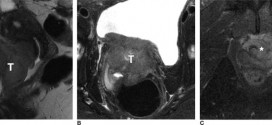

El tumor vesical macroscópicamente (masa extravesical) (T3B). Durante los primeros años de vida de una persona, las células normales se dividen más rápidamente para permitir el crecimiento. El cuerpo está compuesto por billones de células vivas. Las células normales del cuerpo crecen, se dividen formando nuevas células y mueren de manera ordenada. Una vez que se llega a la edad …

El tumor vesical microscópicamente (T3a). Tumor maligno en general. La orina es un líquido formado por agua y sustancias de desecho del organismo. Esta se produce por el filtrado de la sangre en los riñones. A través de unos tubos largos y finos, denominados uréteres, la orina llega a la vejiga y se almacena en ella. La orina, una vez …

El tumor vesical que invade (próstata, útero o vagina (T4a). Tumor maligno en general. Publicado en: binipatia.com Escrito por: Salvador Gregori y Daniel Lynch Etiquetas: salud verdadera, resultados Resumiendo: La vejiga urinaria es un órgano hueco musculo membranoso que forma parte del tracto urinario y que recibe la orina de los uréteres y la expulsa a través de la uretra al exterior …